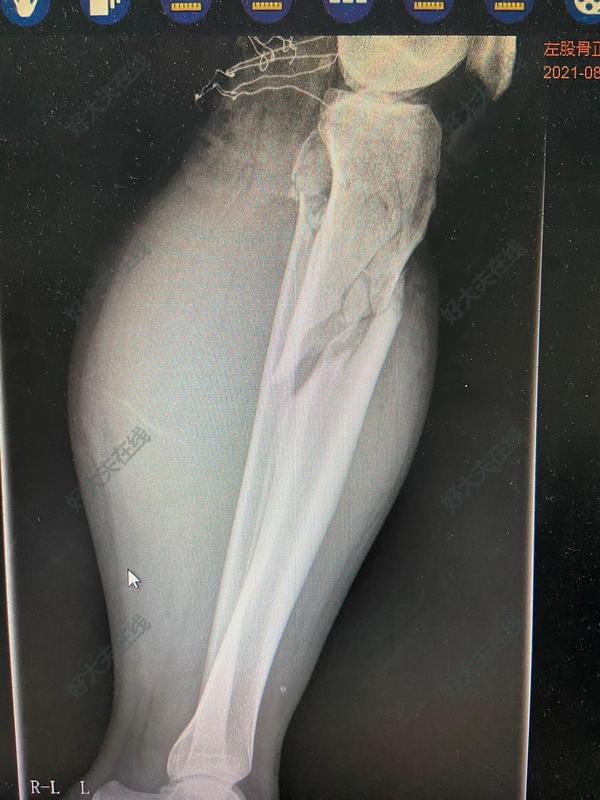

劉娟? 主治醫(yī)師? 鄒平市人民醫(yī)院? 疼痛科1215人已讀 - 精選 左股骨頸、股骨干骨折

治療前 患者男性,35歲,因車禍傷致左股骨頸、股骨干、脛骨近端骨折,左小腿軟組織挫裂傷,GustiloⅢA型。 治療中 急診行清創(chuàng)縫合,骨折牽引。病情穩(wěn)定后,一期行骨折閉合復(fù)位股骨髓內(nèi)釘內(nèi)固定+脛骨近端鋼板內(nèi)固定術(shù)。 治療后 治療后1年 術(shù)后6-9月骨折愈合。治療過程中測試髖ROM:0-120度,膝ROM:0-130度。